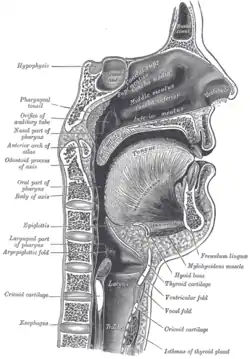

Soft palate without tonsils (after tonsillectomy) Sagittal section of nose mouth, pharynx, and larynx.

The mouth cavity. The cheeks have been slit transversely and the tongue pulled forward. Lateral wall of nasal cavity. (Soft palate visible in lower right)

Lateral wall of nasal cavity. (Soft palate visible in lower right)